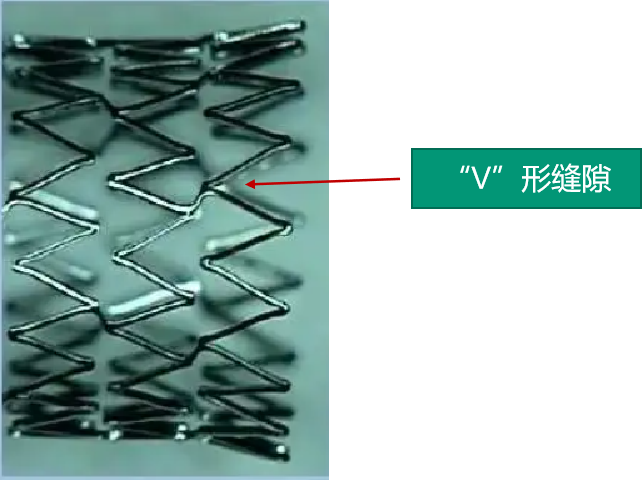

编制支架近端定位困难,编制支架自膨后长度难以把控。因此选用支架选用开环,网孔相对较密的9×30 Precise颈动脉支架。

微导丝卡入开环支架的“V”形缝隙,不能撤出。